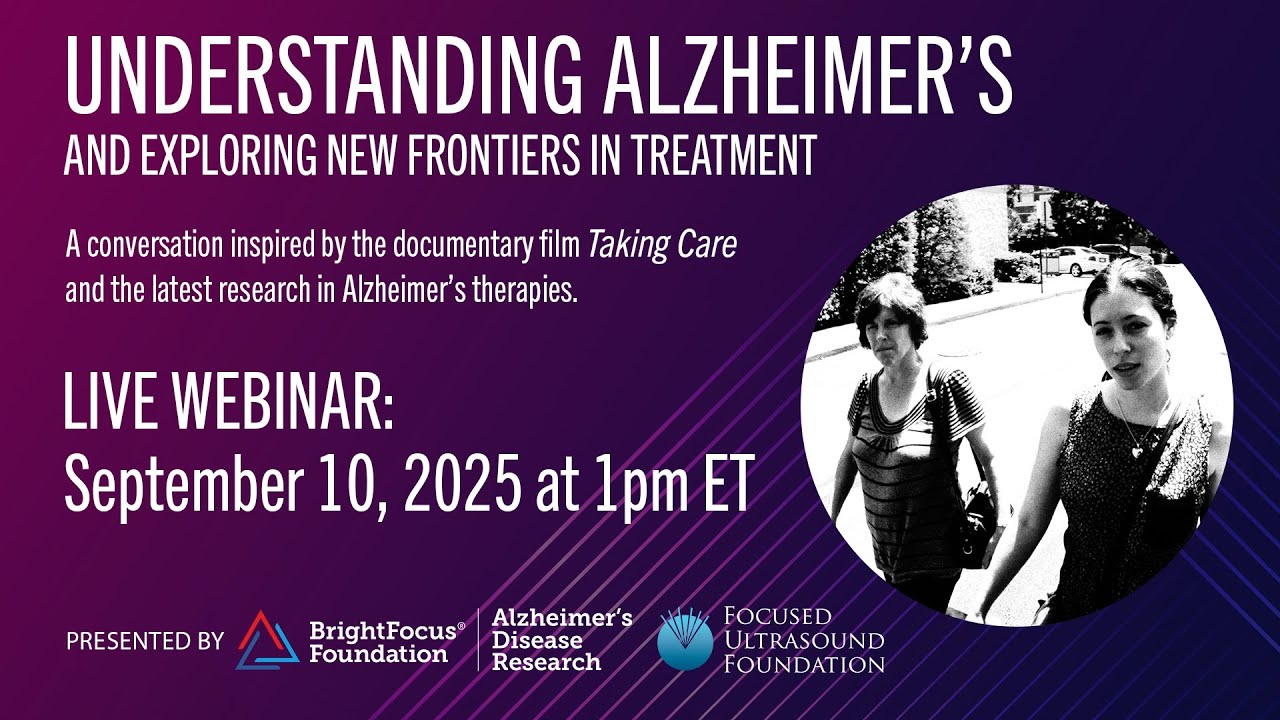

Virtual Programs

Connect With Experts

Explore a variety of programs for people with Alzheimer’s, macular degeneration, and glaucoma to hear directly from experts, ask questions, and build community.

Zoom In on Dementia & Alzheimer’s

A live, interactive virtual discussion series with renowned research scientists and clinicians to keep you informed about the latest brain health breakthroughs and findings.